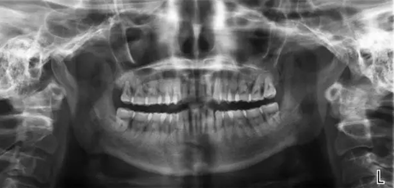

曲斷示:全口牙齒牙槽骨水平吸收根長1/2-2/3。